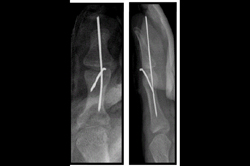

Finger Tip Injury - JESS